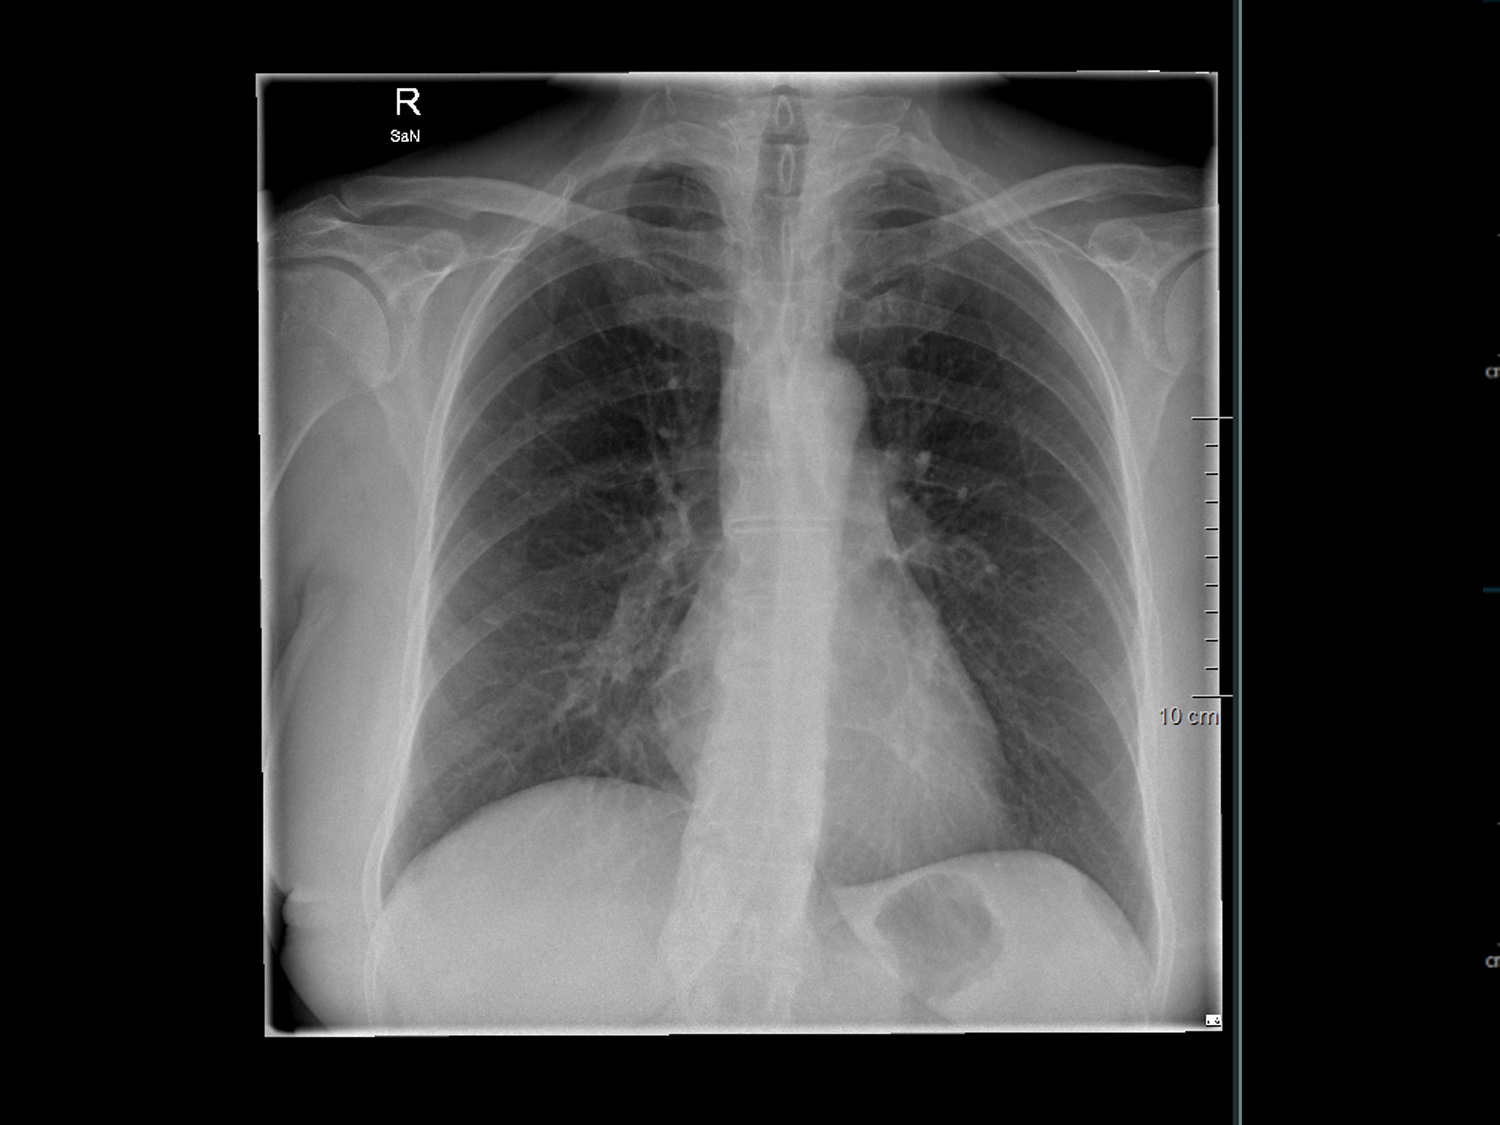

Röntgenuntersuchungen werden für eine Vielzahl von Zwecken eingesetzt, darunter die Diagnose von Knochenbrüchen, die Beurteilung von Organen wie Lunge, Herz und Verdauungstrakt sowie die Untersuchung von Weichteilgewebe auf Anzeichen von Verletzungen oder Erkrankungen. Die Röntgenbildgebung ist schnell, schmerzlos und nicht-invasiv und ermöglicht uns eine schnelle Diagnose und Behandlungsplanung.